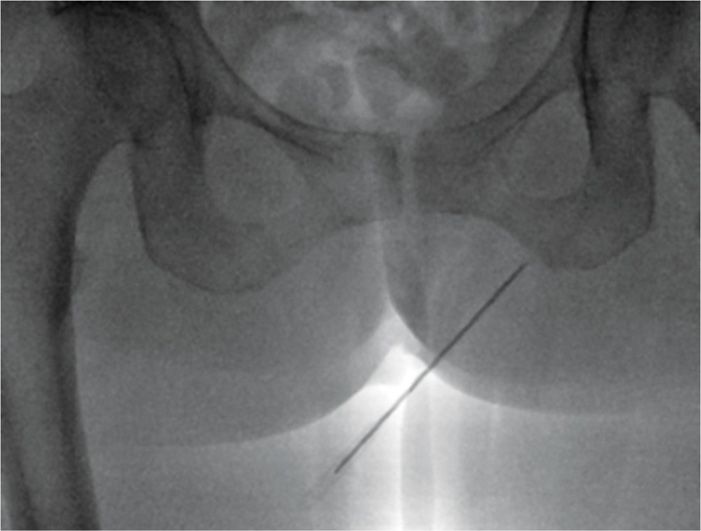

Local Anesthetics Pudendal Block . Pudendal block involves injecting a local anesthetic through the vaginal wall so that the anesthetic bathes the pudendal nerve as it. Blocking the pudendal nerve with injection of local anesthetic is used for vaginal deliveries and for minor surgeries of the vagina. Pudendal and paracervical blocks are nerve blocks used during obstetric and gynecologic procedures. A pudendal block is the anesthetizing of the pudendal nerve that provides sensation to the perineum, anus, vulva, and clitoris using local anesthesia.

Blocking the pudendal nerve with injection of local anesthetic is used for vaginal deliveries and for minor surgeries of the vagina. Pudendal and paracervical blocks are nerve blocks used during obstetric and gynecologic procedures. Pudendal block involves injecting a local anesthetic through the vaginal wall so that the anesthetic bathes the pudendal nerve as it. A pudendal block is the anesthetizing of the pudendal nerve that provides sensation to the perineum, anus, vulva, and clitoris using local anesthesia.

Local Anesthetics Pudendal Block Blocking the pudendal nerve with injection of local anesthetic is used for vaginal deliveries and for minor surgeries of the vagina. Pudendal and paracervical blocks are nerve blocks used during obstetric and gynecologic procedures. Pudendal block involves injecting a local anesthetic through the vaginal wall so that the anesthetic bathes the pudendal nerve as it. A pudendal block is the anesthetizing of the pudendal nerve that provides sensation to the perineum, anus, vulva, and clitoris using local anesthesia. Blocking the pudendal nerve with injection of local anesthetic is used for vaginal deliveries and for minor surgeries of the vagina.